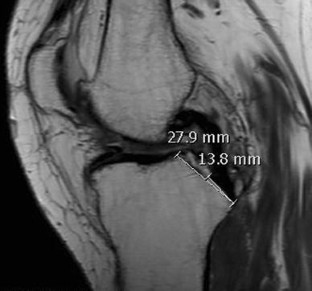

Thirty consecutive female patients suffering from degenerative knee osteoarthritis were included. Two measurements were performed on preoperative MRI images. On sagittal plane, the PCL facet of tibia and the PCL tibial attachment were measured. All 30 patients underwent a TKA using a common CR prosthesis. Postoperatively, the amount of PCL facet resection was measured on the resected tibial plateau using a digital sliding caliper.

In preoperative MRI images, the length of the PCL facet of tibia was found 25.5 ± 2.1 mm and the length of the PCL tibial attachment was 14.5 ± 1.3 mm. The amount of PCL facet resection following TKA was 20.6 ± 2.2 mm on average. This result corresponds to an average resection of 65.1 ± 15.9 % of the PCL tibial attachment following TKA.